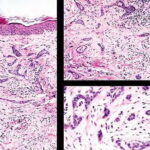

Histopathologic examination reveals a relatively well-circumscribed lesion in the upper two-thirds of the dermis with a focal epidermal connection. It is composed of basaloid aggregations arranged predominantly in columns and cords and admixed with infundibulocystic structures, surrounded by a dense, hypocellular desmoplastic stroma. It may occasionally be difficult to distinguish this entity histologically from malignant desmoplastic lesions such as aggressive growth basal cell carcinoma or MAC. Treatment. Local surgical excision is the preferred treatment